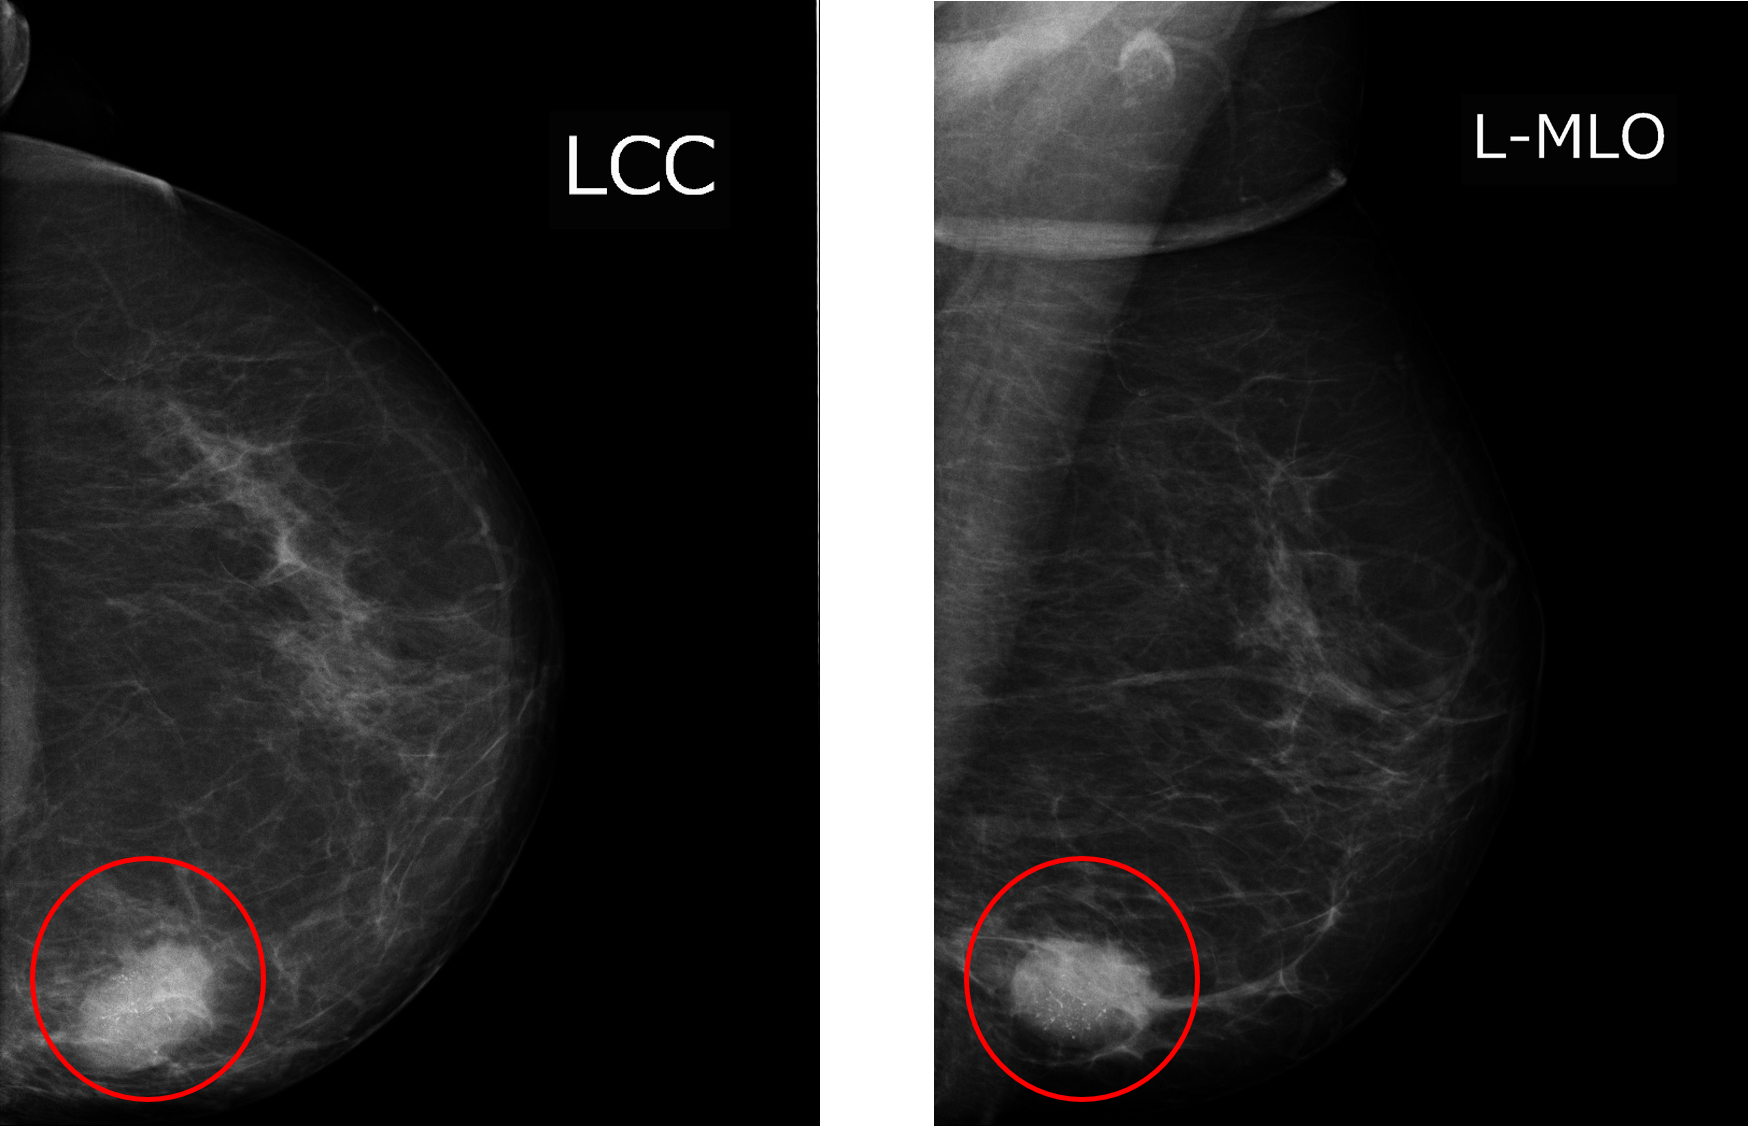

<예> 위 사진은 왼쪽 유방촬영술입니다. 내부의 검은 부분은 대개 지방이고, 넓게 펼쳐진 하얀 부분은 유선 조직입니다. MLO에서 안쪽의 하얀 막대 모양은 대흉근 입니다. 빨간 동그라미로 표시된 하얀색 병변은 나머지 정상 조직과 차이가 있음을 알 수 있습니다. 병변은 CC view에서 아래쪽, MLO view에서 아래쪽이므로 ‘왼쪽 유방의 Lower Inner Quadrant’위치 이므로 Lt. LIQ라고 위치를 말할 수 있습니다.

병변의 위치를 알았다면, 병변의 모양, 경계, 음영, 석회화에 따라 악성인지 양성인지 해석이 필요합니다. 이는 대단히 복잡한 서술이 필요합니다. 유방 영상 판독에는 이를 시스템화 시킨 reporting system이 있는데, BIRADS(Breast imaging-reporting and data system)입니다. 이 방법에 따라 이미지를 해석하고 판독을 하게 됩니다. Category 0~6까지 존재하는데, Category 1은 정상, 5는 암의 가능성이 매우 높음, 6은 암으로 확진된 경우 입니다.